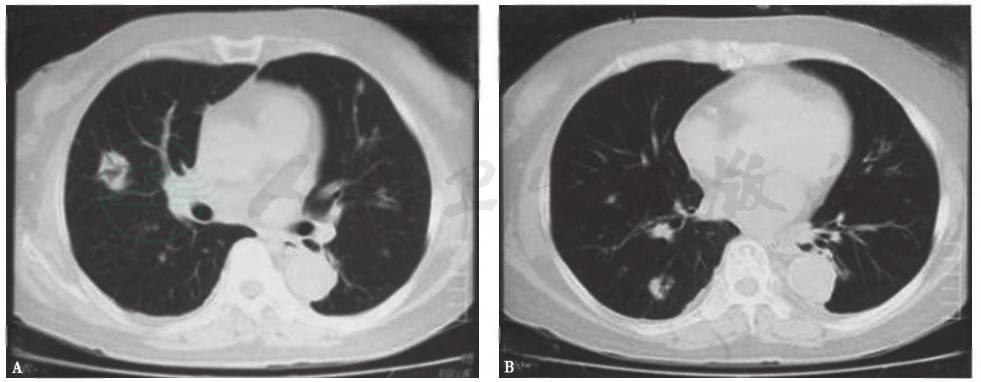

发病第4天,患者于当地医院就诊,胸部CT提示双肺多发结节样改变(图1)。发病第32天,患者转至当地上级医院就诊,胸部CT提示病变较前加重,可见双肺多发大小不一的结节影,部分呈反晕环状,边缘尚清(图2)。

图1发病第4天胸部CT表现

图2发病第32天胸部CT表现